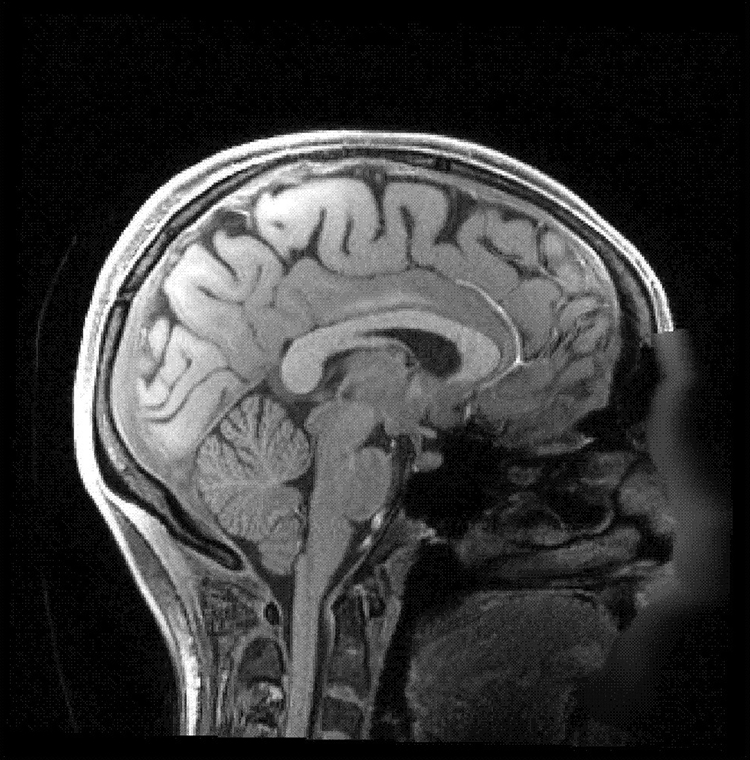

大脑皮层被认为是人们意识活动的主要区域。科学家以为麻醉药就是麻醉这个区域的神经元,使它们不再活跃。新研究发现不是这样,在麻醉药的作用下,这个区域内特定类型的神经元反而变得更加活跃,而且出现同步的活动。

研究称,第五层锥体细胞是大脑皮层主要的信息输出中心,也是皮层不同区域之间联系的桥梁。换句话说,第五层锥体细胞不仅负责皮层内各个区域之间的沟通,也负责皮层与大脑其它区域的沟通。然而,这些细胞的同步活动限制了皮层所能够输出的信息。

以前的研究以为,麻醉状态下,大脑皮层与其它区域的联系被切断导致失去意识。这份新研究了解了产生这项现象更确切的机制:其实是大脑皮层能够输出的信息被减少导致的。